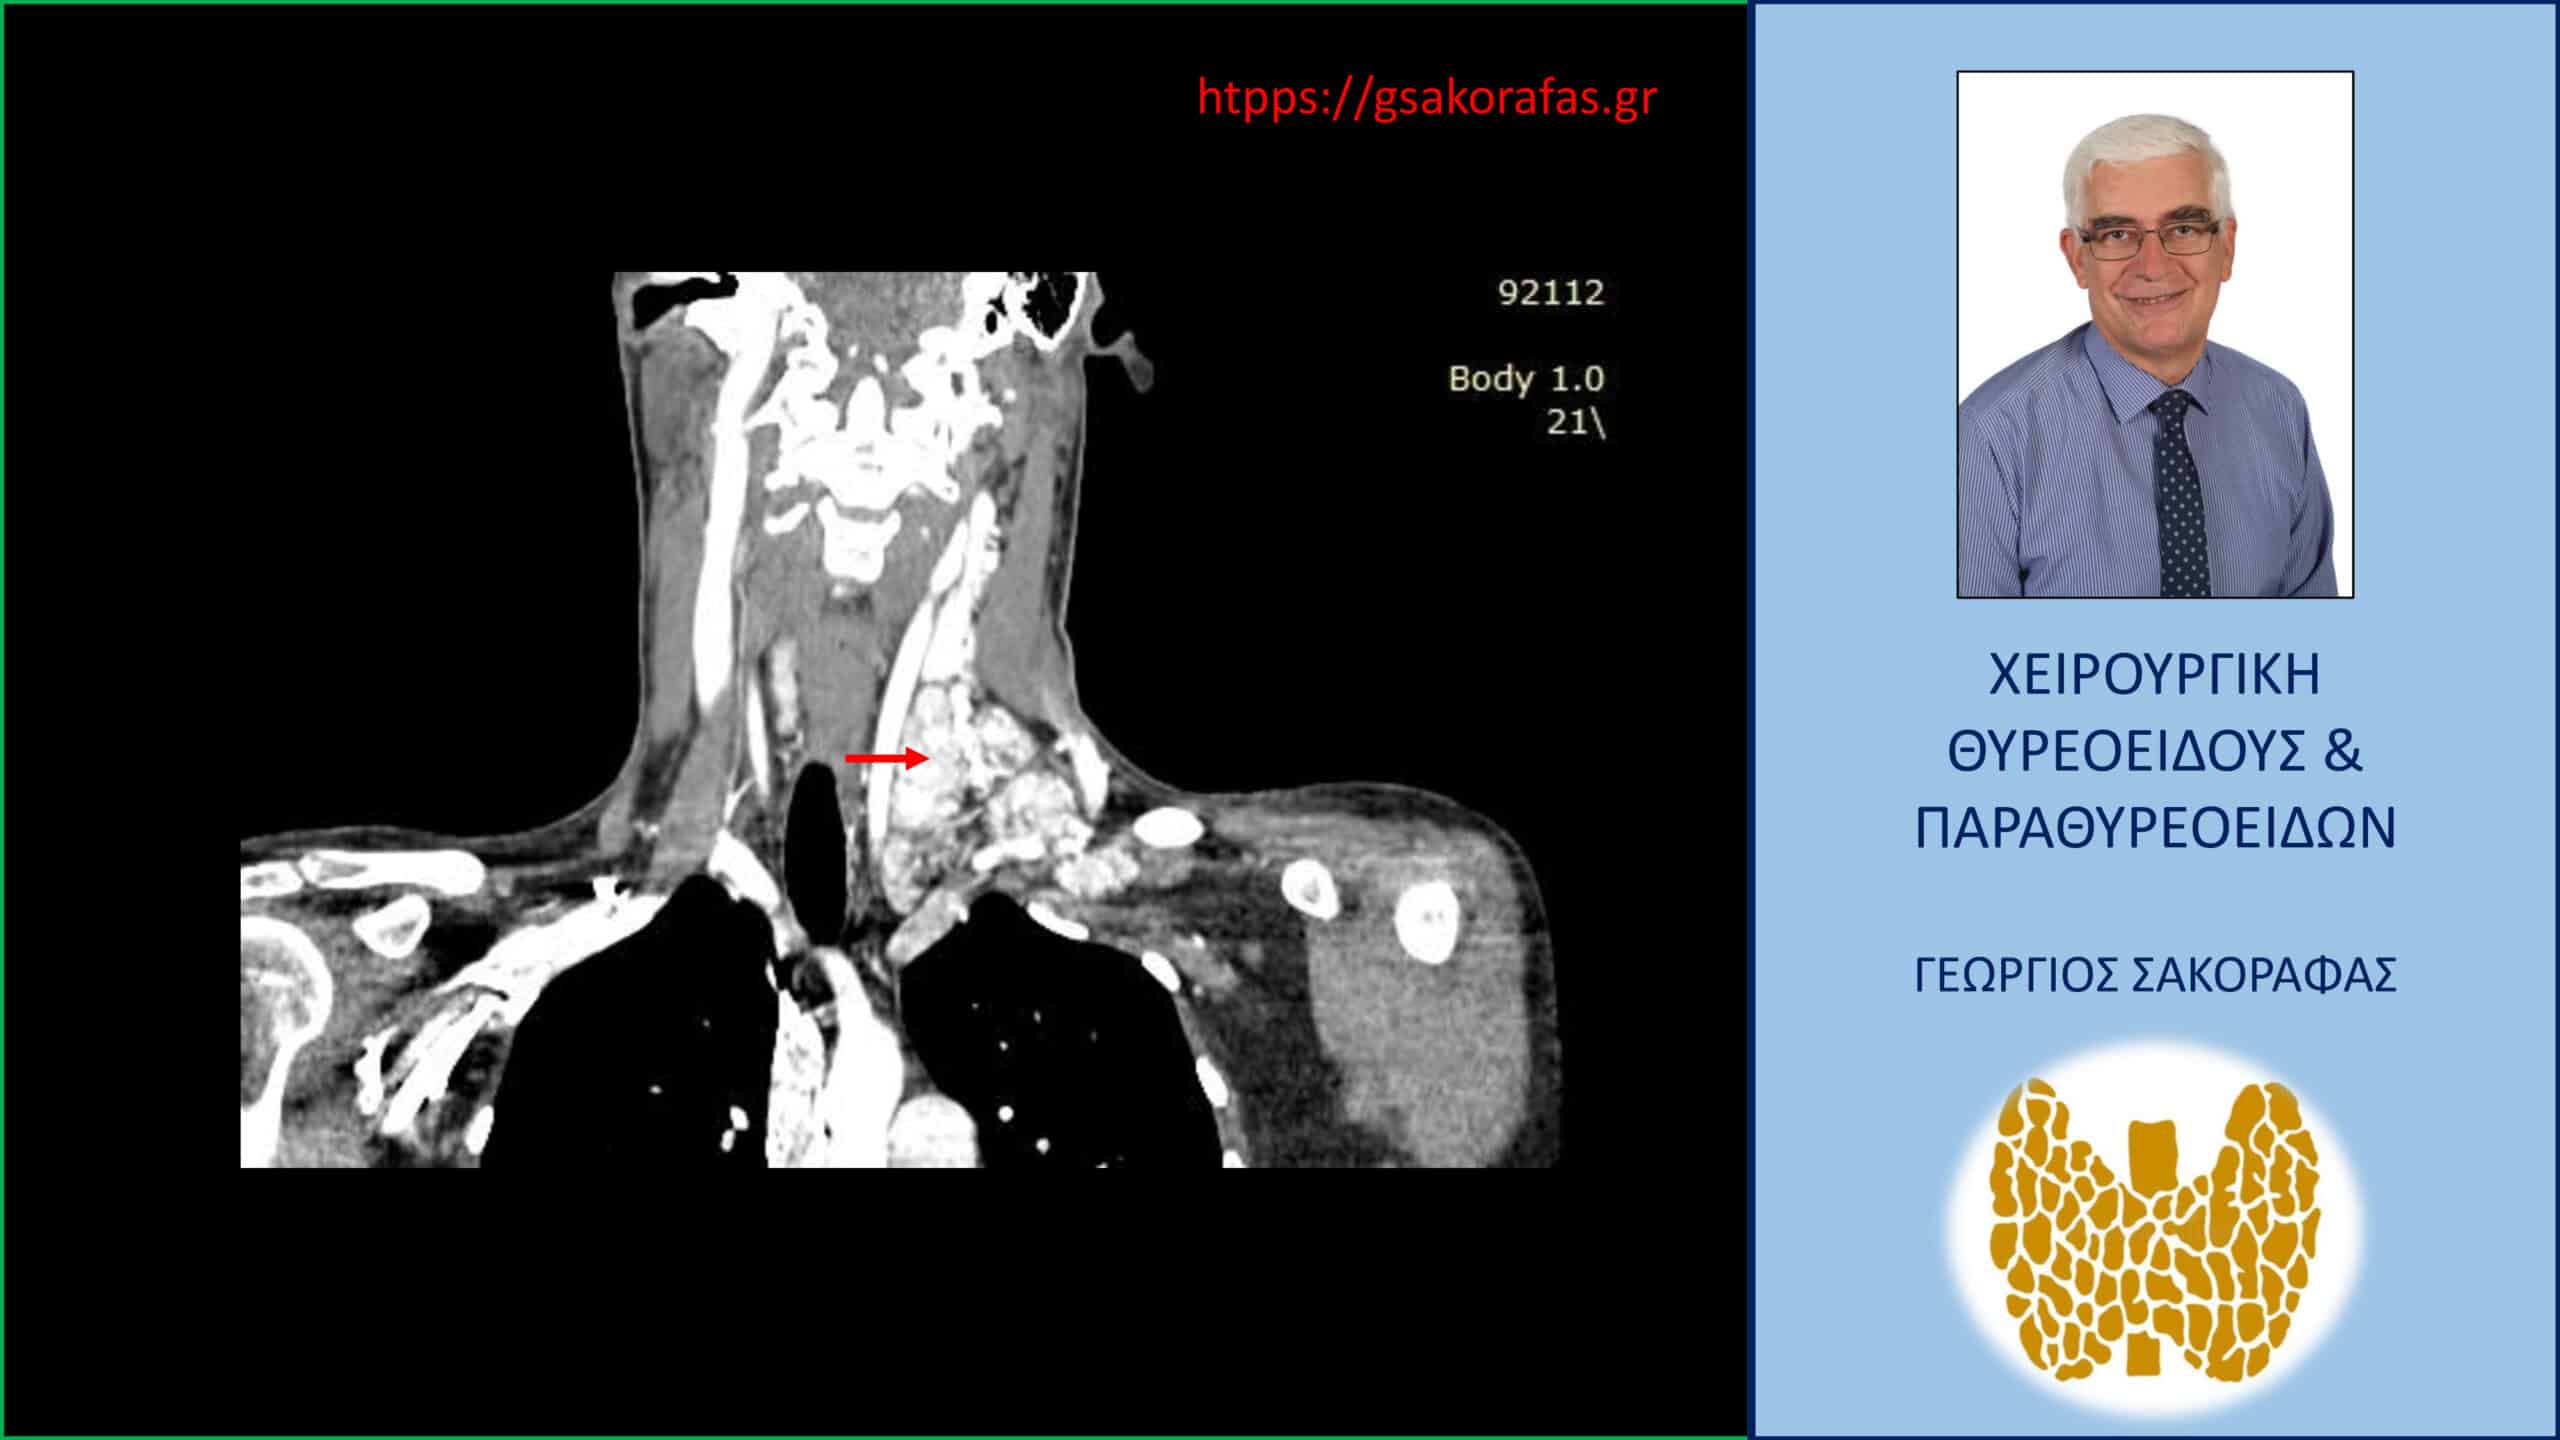

Καρκίνος θυρεοειδούς με εκτεταμένη λεμφαδενική διασπορά – Αξονική τομογραφία – απεικόνιση σε κατά μέτωπο διατομή. Απεικονίζεται η εκτεταμένη λεμφαδενική διασπορά στους λεμφαδένες της αριστερής πλάγιας τραχηλικής χώρας. Το κόκκινο βέλος έχει τοποθετηθεί περίπου στο κέντρο της εκτεταμένης λεμφαδενικής διασποράς, που εκτείνεται σε μεγάλη έκταση επί τα εκτός των μεγάλων αγγείων του τραχήλου.

Αξονική τομογραφία – απεικόνιση σε κατά μέτωπο διατομή. Απεικονίζεται η εκτεταμένη λεμφαδενική διασπορά στους λεμφαδένες της αριστερής πλάγιας τραχηλικής χώρας. Το κόκκινο βέλος έχει τοποθετηθεί περίπου στο κέντρο της εκτεταμένης λεμφαδενικής διασποράς, που εκτείνεται σε μεγάλη έκταση επί τα εκτός των μεγάλων αγγείων του τραχήλου.